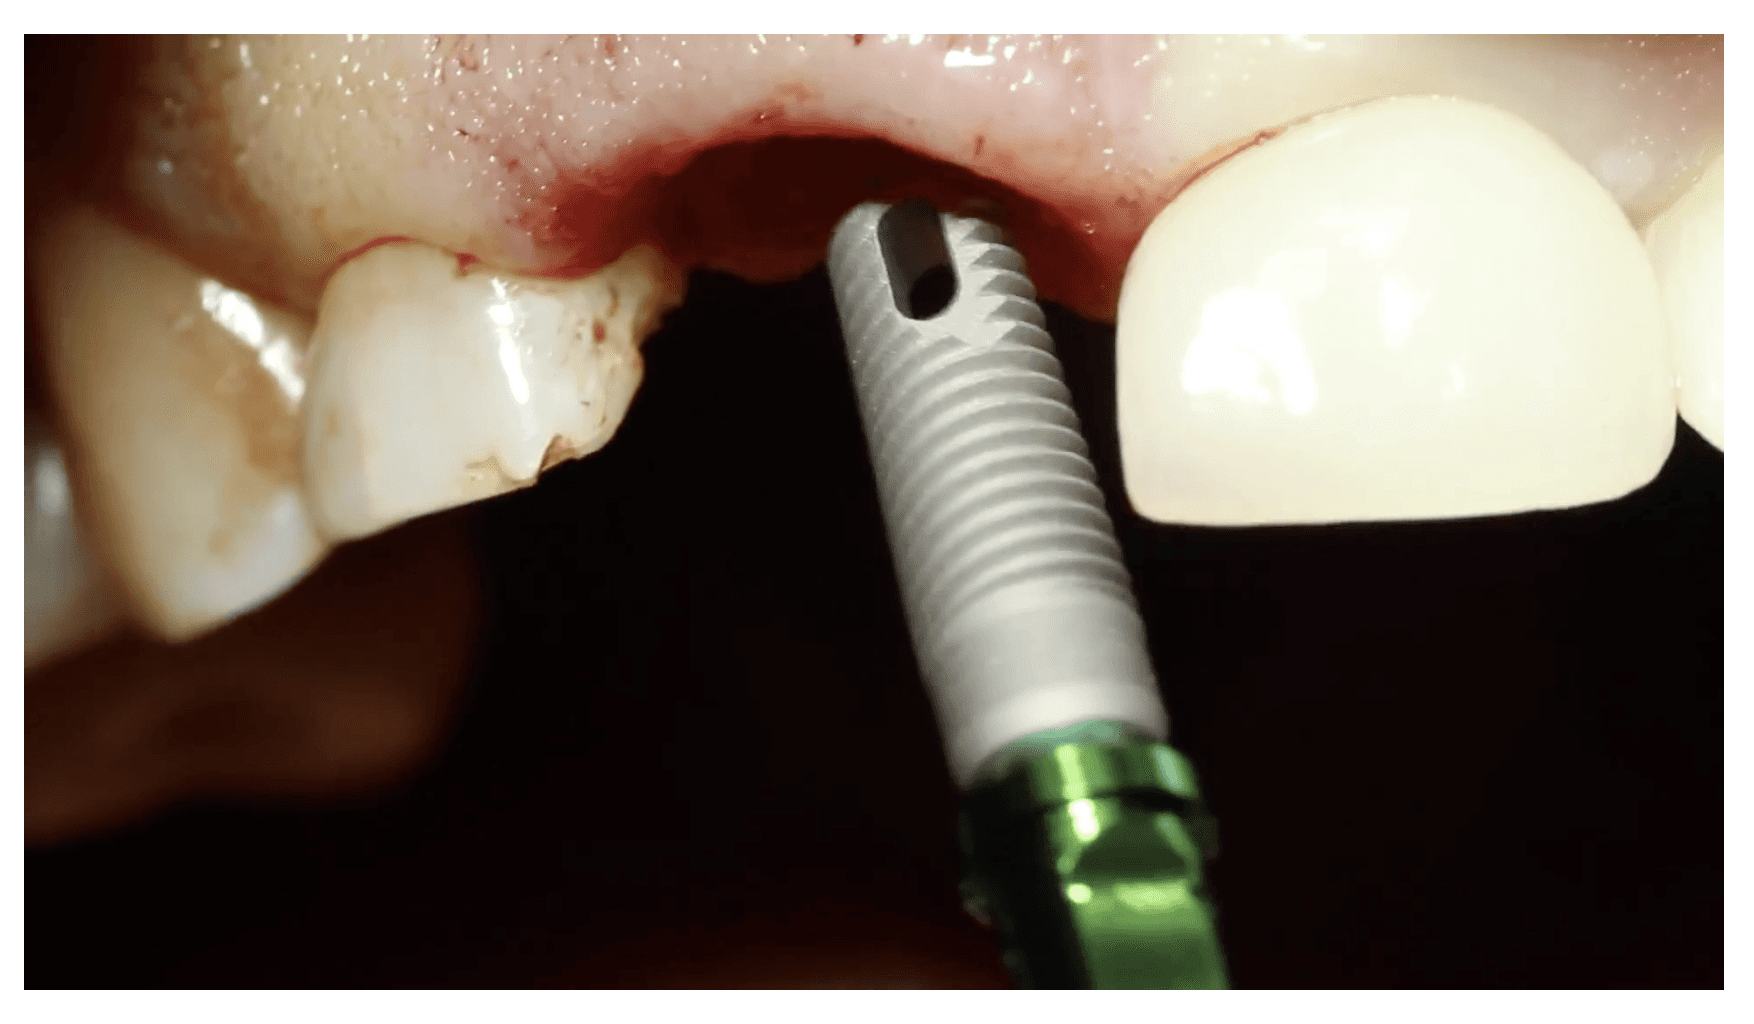

➡️ Step-by-Step Surgical Technique Videos

➡️ Benchtop Demonstrations